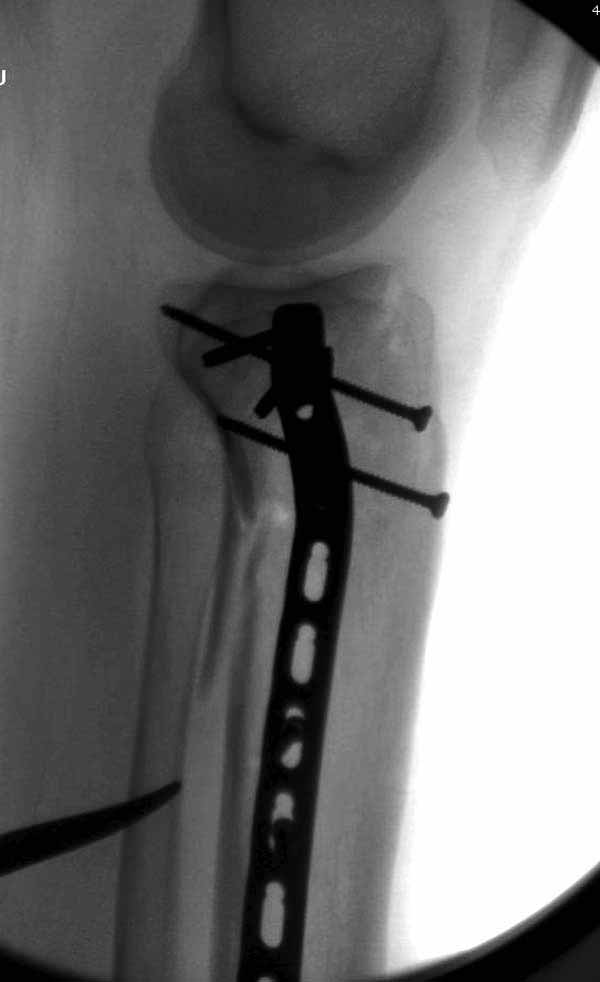

В приложении этапы фиксации пластиной Synthes для плеча при переломе медиального мыщелка.

Имя     : 7 medial column tibial plateau.JPG

Тип     : image/jpg